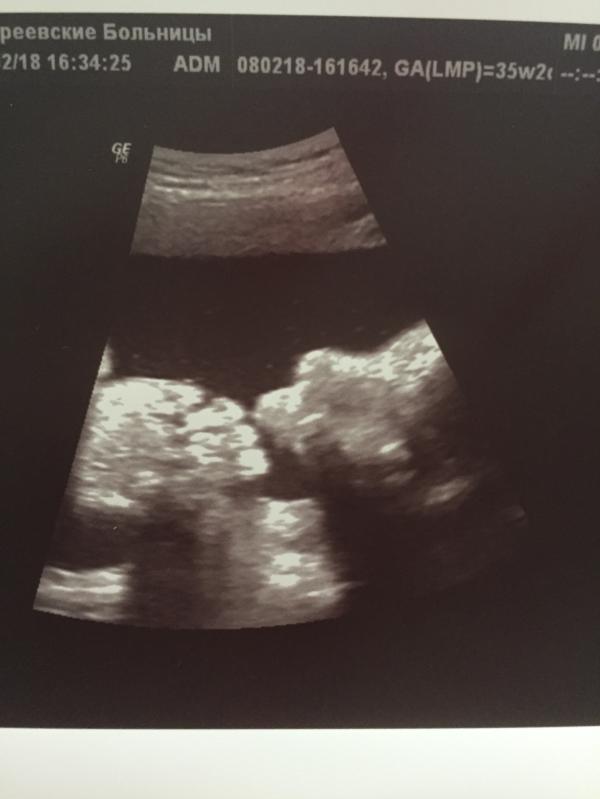

Началась 37 неделя, малыш перевернулся вниз головой, как сказал врач " готов к эвакуации"🙂! Плацента поднялась, правда 3 степени зрелости, кровоток не нарушен!Вес малыша в 36 недель 2840, все показатели в норме, что не может не радовать!👏Так что готовимся к естественным родам!

Я очень люблю ходить на УЗИ)) да ещё и малыш вчера повеселил, то гримасничал, то кулаки в рот засовывал, а под конец вообще решил пососать палец на ноге😁